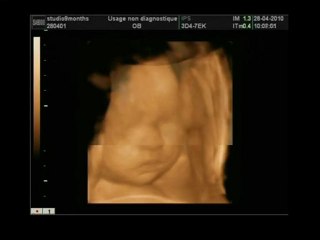

Echographie Souvenir 3D 4D chez Baby Live Montpellier